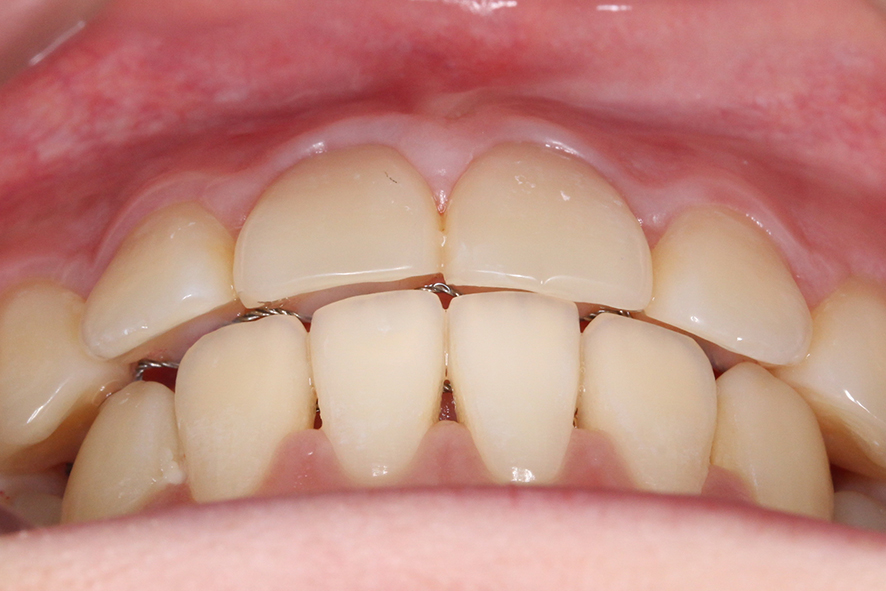

overjet 사진을 보면 돌출감이 심해 보이지

않았던 정면 및 overbite 사진과 달리

상악의 뻐드러짐이 심한 모습인데요,

구치부 교합을 확인해봐야 알겠지만

상악이 과하게 발달한 2급 부정교합

증상이 있을 것으로 보입니다.

이러한 전치부 교합 상태를 가진 분들의 경우

상하악 앞니가 서로 맞닿지 않기 때문에

아래 앞니에 의해 윗니의 설측면이

손상될 가능성이 있습니다.

또한 음식을 드실 때 치아의 절단력을

사용하기 어렵기 때문에 혀를 내밀어

절단하는 경우가 있는데요,

이러한 습관이 지속된다면

치아의 돌출이 더 악화될 가능성이 있습니다.